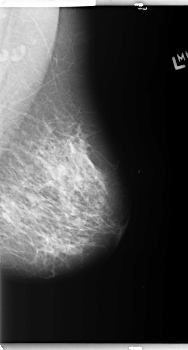

B_3148_1.RIGHT_MLO

RIGHT_MLO LINES 5960 PIXELS_PER_LINE 3680 BITS_PER_PIXEL 12 RESOLUTION 50 OVERLAY

FILE: B_3148_1.RIGHT_MLO.OVERLAY

TOTAL_ABNORMALITIES 2

ABNORMALITY 1

LESION_TYPE CALCIFICATION TYPE AMORPHOUS-PLEOMORPHIC DISTRIBUTION CLUSTERED

ASSESSMENT 4

SUBTLETY 2

PATHOLOGY BENIGN

TOTAL_OUTLINES 1

BOUNDARY

ABNORMALITY 2